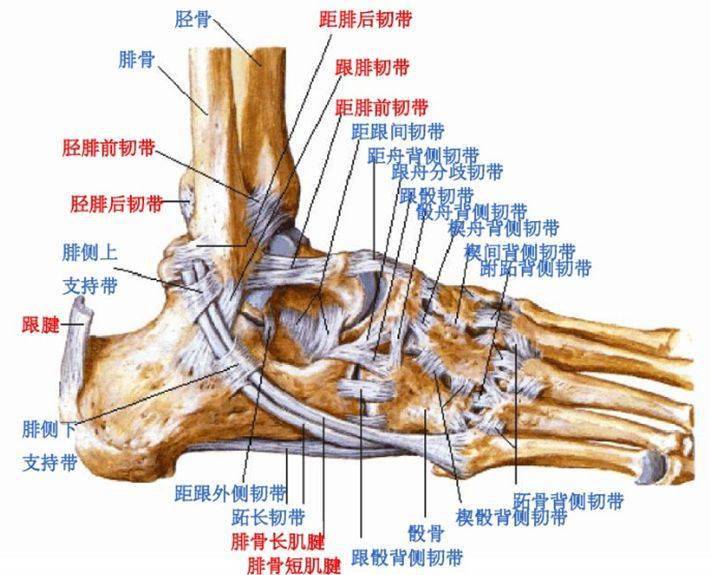

高清图解踝关节韧带解剖

踝关节解剖分析

值得收藏踝关节解剖分析高清图文详解

踝关节损伤的病因如何处理以及预防措施(附踝关节解剖

踝关节损伤的病因如何处理以及预防措施(附踝关节解剖